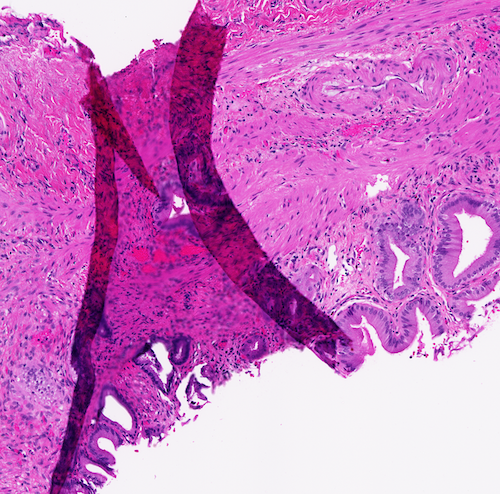

Regardless whether we use digitization or microscopy, the presence of artifacts such as folded tissue might negatively affect the diagnosis [4]. When digital technology is used other artifacts like blur may also reduce the quality of computerized algorithms [10]. Tissue fold can occur in the sectioning part of tissue processing when a thin tissue slice is folded [11]. Figure 1 shows three samples of folded tissue.

[5pt] \stackunder[5pt]

\stackunder[5pt] \stackunder[5pt]

\stackunder[5pt]